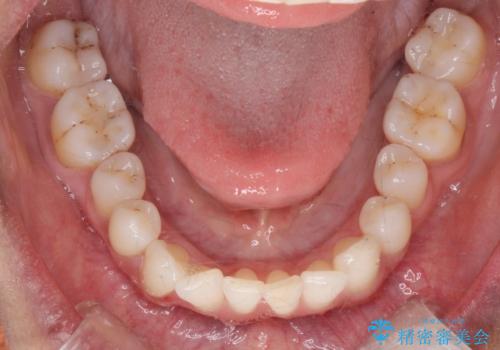

着色が気になる(エアフロー)

- 着色が気になるとの事で来院。

エアフローでしっかり着色を取り除きました。

着色が目立たなくなり大変満足して頂けました。